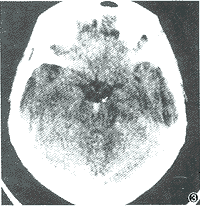

腦水腫間質性腦水腫:多見於梗塞性腦積水,由於腦脊液不能研究員通過正常途徑吸收,這類水腫主要會議發生於腦室的周圍白質,也稱為積水性腦水腫,由於腦室擴大,室管膜擴張,腦室表面結構及通透性改變,部分腦脊液逸出腦室擠入附近的白質,故腦室內腦脊液壓力的高低可直接影響此類腦水腫的程度,CT腦掃描可見室管膜吸收大量腦脊液,腦室周圍白質,尤其額角周圍,呈蝴蝶狀低密度區,臨床副教授上常見於各種原因所致的急或獲得慢性梗阻性腦積水,若能及時行腦室分流術,則腦水腫很快消失。